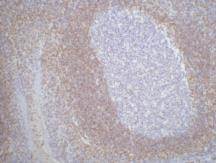

Mouse Monoclonal CD45 Antibody

中文名:CD45抗体

Catalog:IPDX20769

Size: 50μl / 100μl

Application: WB IF IHC ICC FCM Elisa

Reactivity:Human,Mouse,Rat

Synonyms:GP180; L CA; CD45 antigen

Type:Primary antibody